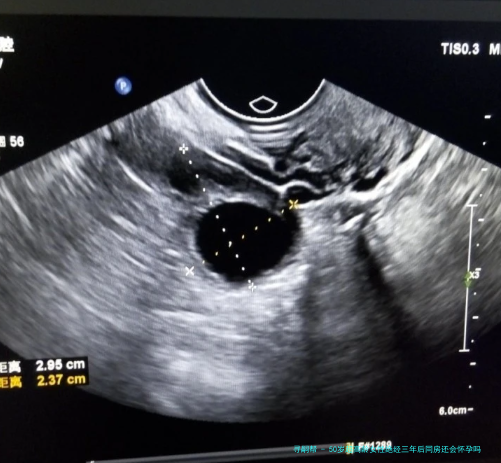

上一次看1个新闻说是大龄女性绝经后仍然怀孕,我就记忆挺不堪设想的,我原本来是不信的,但是我怕无数朋友都说是有这种案例存在的,但是我在想不是闭经随后,卵巢功效会下降吗,不是应该相比难以怀孕了呀,并且也不来大例假了,为什么还会出现这类情况呀,有姐妹知道上了50岁的超高龄女性,在绝经三个年头后又会怀孕吗?